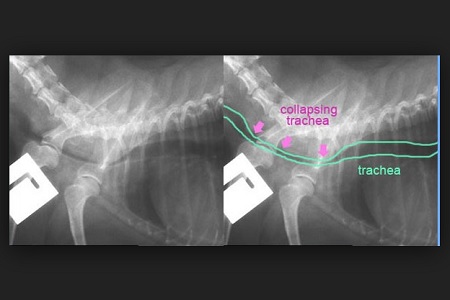

Un collasso tracheale è abbastanza semplice da riconoscere, proprio perché il “verso d’anatra” è tipico di questo problema. Oltre alla visita clinica, il veterinario effettuerà una radiografia per verificare la presenza di un restringimento della trachea.collasso tracheale radiografia

In alcuni animali, gli anelli che compongono la trachea si indeboliscono sempre di più con il passare del tempo fino a schiacciarsi, restringendo così il lume della trachea. In poche parole, sembra quasi che la cartilagine non riesca più a mantenere la forma più o meno cilindrica, creando piuttosto un tubo che si ripiega dall’alto verso il basso. In questo modo l’aria non riesce più ad arrivare facilmente ai polmoni, provocando una difficoltà respiratoria più o meno grave.